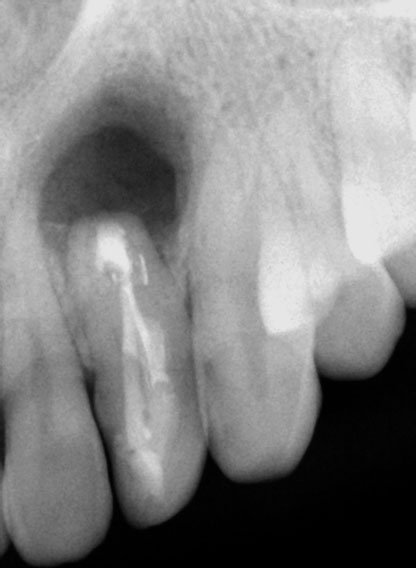

Pre-op:

Central incisor referred after previous clinician had accessed the tooth and was unable to locate the calcified canal.

Removal of temporary restoration shows palatal perforation (red arrow) and a calcified canal in the middle (yellow arrow)

Palatal perforation was supra-crestal and was repaired with GIC

Calcified canal located

Calcium hydroxide placed

Recall after 10 days. Sinus tract healed

Post-op & 1 year recall

Pre-op, Post-op & 1 year recall